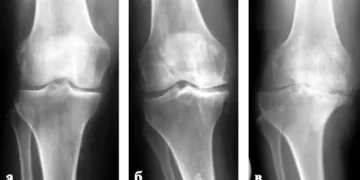

Как эксперт в области медицинской визуализации, я могу с уверенностью сказать, что снимок коленного сустава с артрозом демонстрирует характерные изменения, которые значительно помогают в диагностике данного заболевания. На рентгенограммах мы часто можем увидеть сужение суставной щели, что является одним из основных признаков артроза. Также в изображениях могут быть замечены остеофиты – края костей, которые образуются как результат хронического воспаления и износа сустава. Эти изменения говорят о прогрессирующем разрушении хряща и сопутствующих структур.

Кроме того, важно отметить, что различные стадии артроза могут различаться по уровню выраженности этих признаков. На начальных стадиях может наблюдаться минимальное сужение суставной щели и незначительные остеофиты, тогда как при более выраженной стадии наблюдается значительное разрушение хрящевой ткани, а также выраженные изменения в костной ткани вокруг сустава. Эти визуальные данные позволяют врачам не только ставить диагноз, но и определять степень тяжести заболевания, что критически важно для выбора эффективной терапии.

На ранней стадии заболевания рентгеновский снимок демонстрирует незначительное сужение суставной щели. Это можно определить, сравнивая с параллельным суставом. Причиной этого является дистрофия хрящей.

На втором этапе артроза изображение показывает более заметное сужение суставной щели, которое может быть значительно меньше, чем у здорового сустава. На снимке видно, что хрящи повреждены в тех областях, где на них было оказано значительное давление. Костные разрастания становятся отчетливо видимыми. В районе, где щель значительно сужена, развивается остеосклероз. Эти изменения указывают на наличие остеохондроза.

На последующей стадии рентгенографическое исследование демонстрирует явно выраженные признаки патологии. Хрящи почти полностью разрушены. Наблюдается деформация суставных поверхностей. Из-за увеличения площади разрастаний происходит уплотнение тканей.

На рентгеновских снимках коленного сустава в начальной стадии артроза могут отмечаться легкие изменения, такие как сужение суставной щели и начало разрушения хряща. По мере прогрессирования заболевания становятся видимыми более серьезные изменения: утрата хряща приводит к увеличению костного контакта, образованию остеофитов и изменению контуров костей. На поздних стадиях рентгенография может показать обширные разрушения коленного сустава, а также деформацию и изменение положения костей. Важно отметить, что степень выраженности симптомов не всегда коррелирует с величиной изменений на снимках — у некоторых пациентов с серьезными рентгенологическими проявлениями может быть лишь незначительный болевой синдром, в то время как у других с минимальными изменениями может быть выраженная боль.